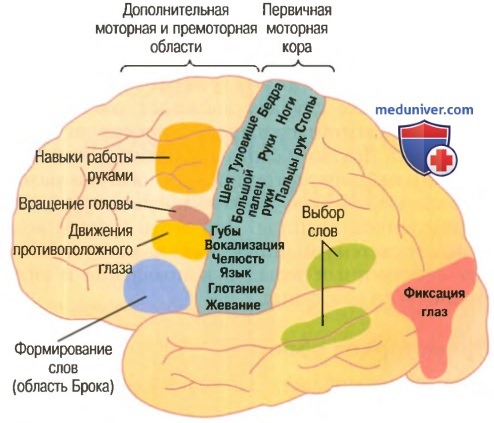

Схема чувствительных зон новой коры мозга